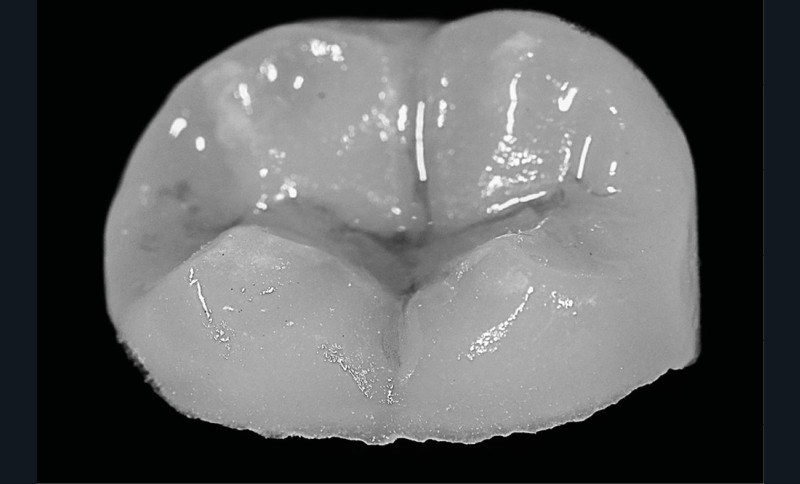

Concernant la reconstruction prothétique, nous avons réalisé une base intermédiaire avec du composite fibré afin de limiter la propagation de la fissure (Sablage, MR3, composites Flow, composite fibré, composite microhybride) [7]. On décide de recourir à un overlay de renforcement en disilicate de lithium afin de réaliser un recouvrement cuspidien pour deux raisons principales. La première étant la profondeur de la cavité d’accès, qui dépasse le plan d’inflexion de la dent et qui amplifie le risque de fracture. La deuxième étant que, de par sa préparation en biseau, l’overlay va diriger les forces occlusales principalement vers le centre de la dent et donc contenir au mieux cette fissure [8] (fig. 9 et 10).